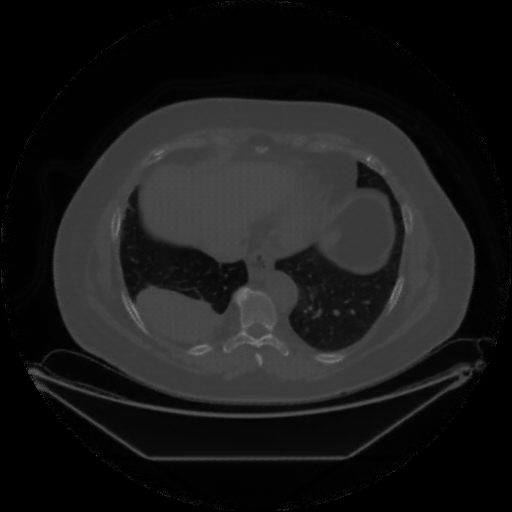

Generated VENOUS CT scan (A→B translation)

Full window (WL 1023.5, WW 4095 β†’ Low βˆ’1024, High +3071)

Lung window (WL -600, WW 1500 β†’ Low βˆ’1350, High +150)

Mediastinum window (WL 40, WW 400 β†’ Low βˆ’160, High +240)